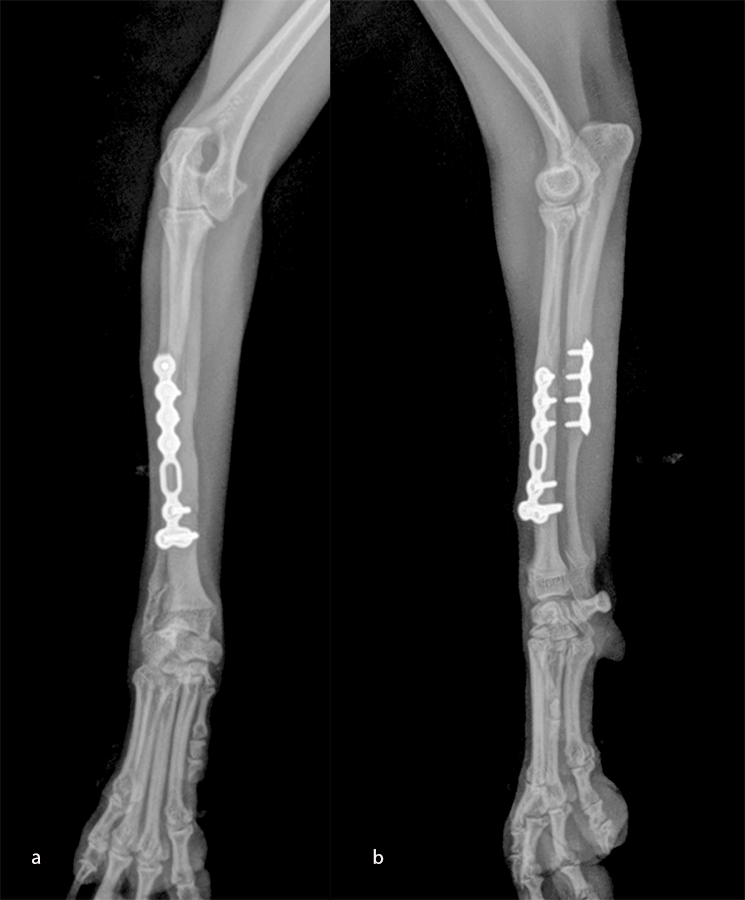

Open reduction and internal fixation of distal radial and ulna fractures with a 1.3 radial plate and a 1.3 ulnar plate (Fig 10).

An open but do-not-touch approach was performed, and the plate was fixed with both cortex screws and locking screws for both plates (Fig 12). After 4 months, the fractures were totally healed with normal bone growth and the dog had a complete functional recovery (Fig 13).